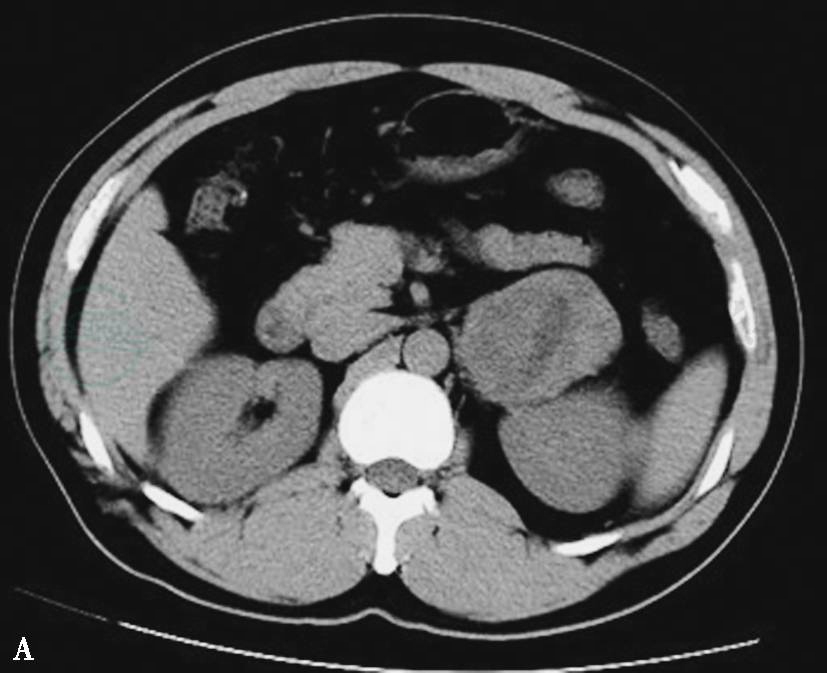

图3两侧肾上腺嗜铬细胞瘤

A.CT平扫示两侧肾上腺类圆形瘤体,密度尚均匀;B.CT平扫示两侧肾上腺瘤体,右侧瘤体不规则分叶状,左侧瘤体呈类圆形,其内囊变较明显